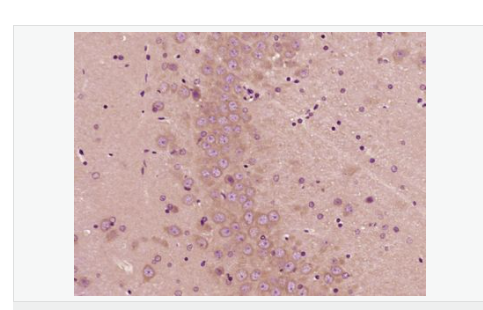

| 產(chǎn)品應(yīng)用 | ELISA=1:5000-10000 IHC-P=1:100-500 IHC-F=1:100-500 IF=1:100-500 (石蠟切片需做抗原修復(fù)) not yet tested in other applications. optimal dilutions/concentrations should be determined by the end user. |

| 產(chǎn)品介紹 | PBR (Peripheral type Benzodiazepine Receptor) is a ubiquitous protein (18 kDa) found in most steroidogenic tissues. It is located primarily in the outer mitochondrial membrane of steroid producing tissues and is found in association with a 34 kDa voltage dependent anion channel protein (VDAC). PBR interacts with some benzodiazepines and has different affinities than its endogenous counterpart. PBR appears to be a key factor in the transport of cholesterol from the outer to the inner mitochondrial membrane to permit the initiation of steroid hormone synthesis. It is thought to be part of the mitochondrial permeability transition pore (PT) and to be involved in apoptosis. It is speculated that patients with congenital lipoid adrenal hyperplasia, who cannot make any steroids, might have a genetic lesion in BZRP. A short form, PBRS is also expressed in the same tissues, but at a level about ten times that of PBR. Function: Responsible for the manifestation of peripheral-type benzodiazepine recognition sites and is most likely to comprise binding domains for benzodiazepines and isoquinoline carboxamides. May play a role in the transport of porphyrins and heme. Plays a role in the transport of cholesterol across mitochondrial membranes in steroidogenic cells. Subcellular Location: Mitochondrion membrane. Tissue Specificity: Found in many tissue types. Expressed at the highest levels under normal conditions in tissues that synthesize steroids. Similarity: Belongs to the TspO/BZRP family. SWISS: B1AH88 Gene ID: 706 Database links: Entrez Gene: 706 Human Entrez Gene: 12257 Mouse Omim: 109610 Human SwissProt: B1AH88 Human SwissProt: P30536 Human SwissProt: P50637 Mouse Unigene: 202 Human Unigene: 1508 Mouse Important Note: This product as supplied is intended for research use only, not for use in human, therapeutic or diagnostic applications. 地西泮結(jié)合抑制因子; DBI能拮抗安定物質(zhì):diazepam與腦突觸膜相結(jié)合 ,故稱之為安定結(jié)合抑制蛋白(DBI),地西泮結(jié)合抑制因子(diazepam binding inhibitor,DBI)具有抑制由葡萄糖誘導(dǎo)的胰島素分泌、促進膽固醇跨線粒體膜轉(zhuǎn)運和調(diào)節(jié)脂肪酸合成與代謝等多種生理功能。 |